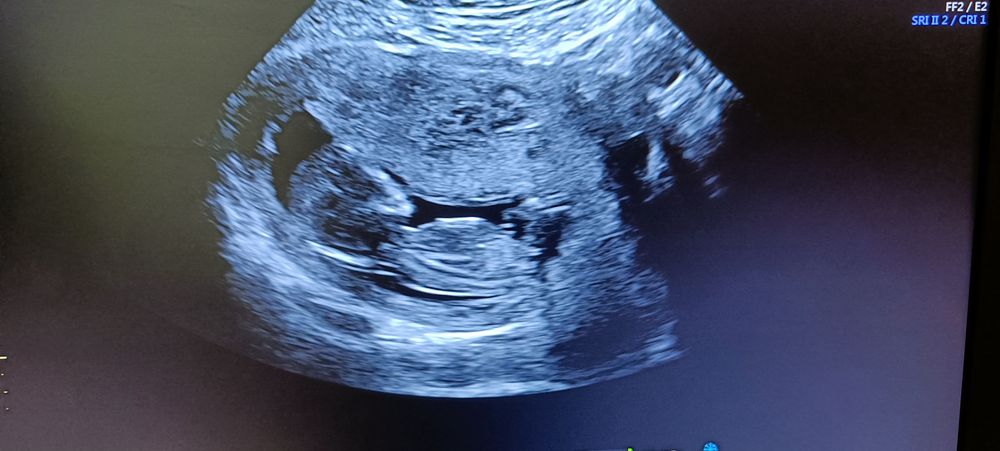

Лисица в Благополучная беременность 3 года Гадание на пол по УЗИ 13,3 недели УЗИ, КТГ, доплер Вот и первый скрининг! Что видно? Погадаем? Посмотрите еще 20 записей на эту тему Отменить Ответить Алина Девчуля, точно) 27.08.2022 Ответить Сентябринхен Я бы тоже сказала девочка! 23.08.2022 Ответить Маргарита Девочка❤️ 23.08.2022 Ответить Евгения Девочка 23.08.2022 Ответить Ксения Пискарева У знакомой похожее узи, у неё мальчик)) я за мальчика)) 23.08.2022 Ответить Леди баг Девочка 23.08.2022 Ответить Леди баг Если это бугорок половой, то по его наклону-девочка. 23.08.2022 Ответить УЗИ на 36 неделе Не разбираюсь в этом, врач молчит Чаты Беременных Выберите чат: Январята-2026 Февралята-2026 Мартята-2026 Апрелята-2026 Майчата-2026 Июнята-2026 Июлята-2026 Августята-2026